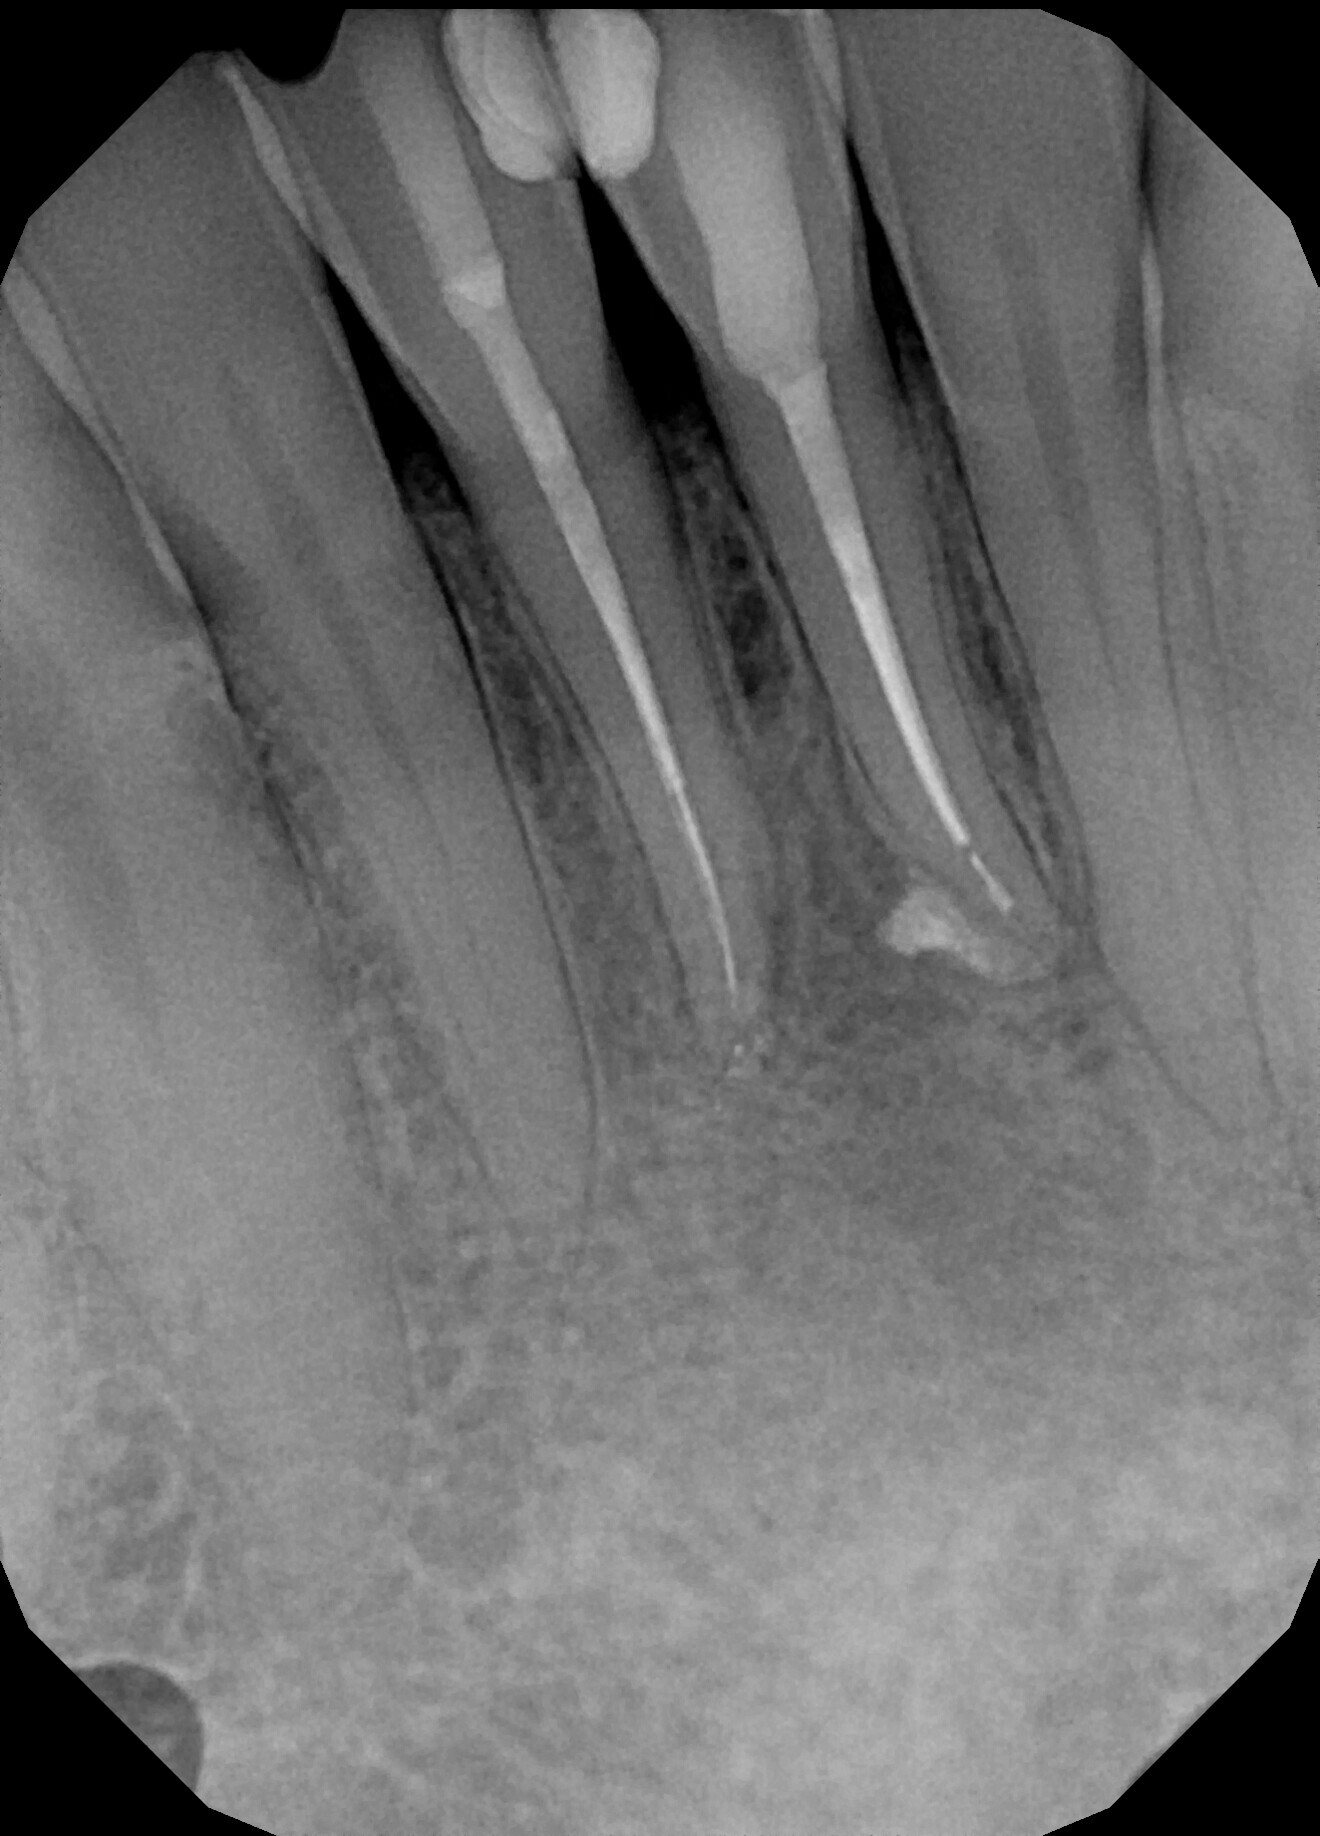

Instrumentation was then performed with the R25 RECIPROC blue up to the level of the split, and the split was prepared with the 12.5/0.04 R-PILOT (VDW; Fig. 18). The final irrigation protocol was performed with copious amount of fluids (sodium hypochlorite and citric acid with a final rinse of distilled water; Fig. 19). Obturation was performed with the piston technique, and the restoration was done with composite material (Fig. 20). The patient was referred to the prosthodontist for final restoration. On the final CBCT scan, it was clearly visible that the piston technique had helped to obturate the deep split in the apical area (Fig. 21).